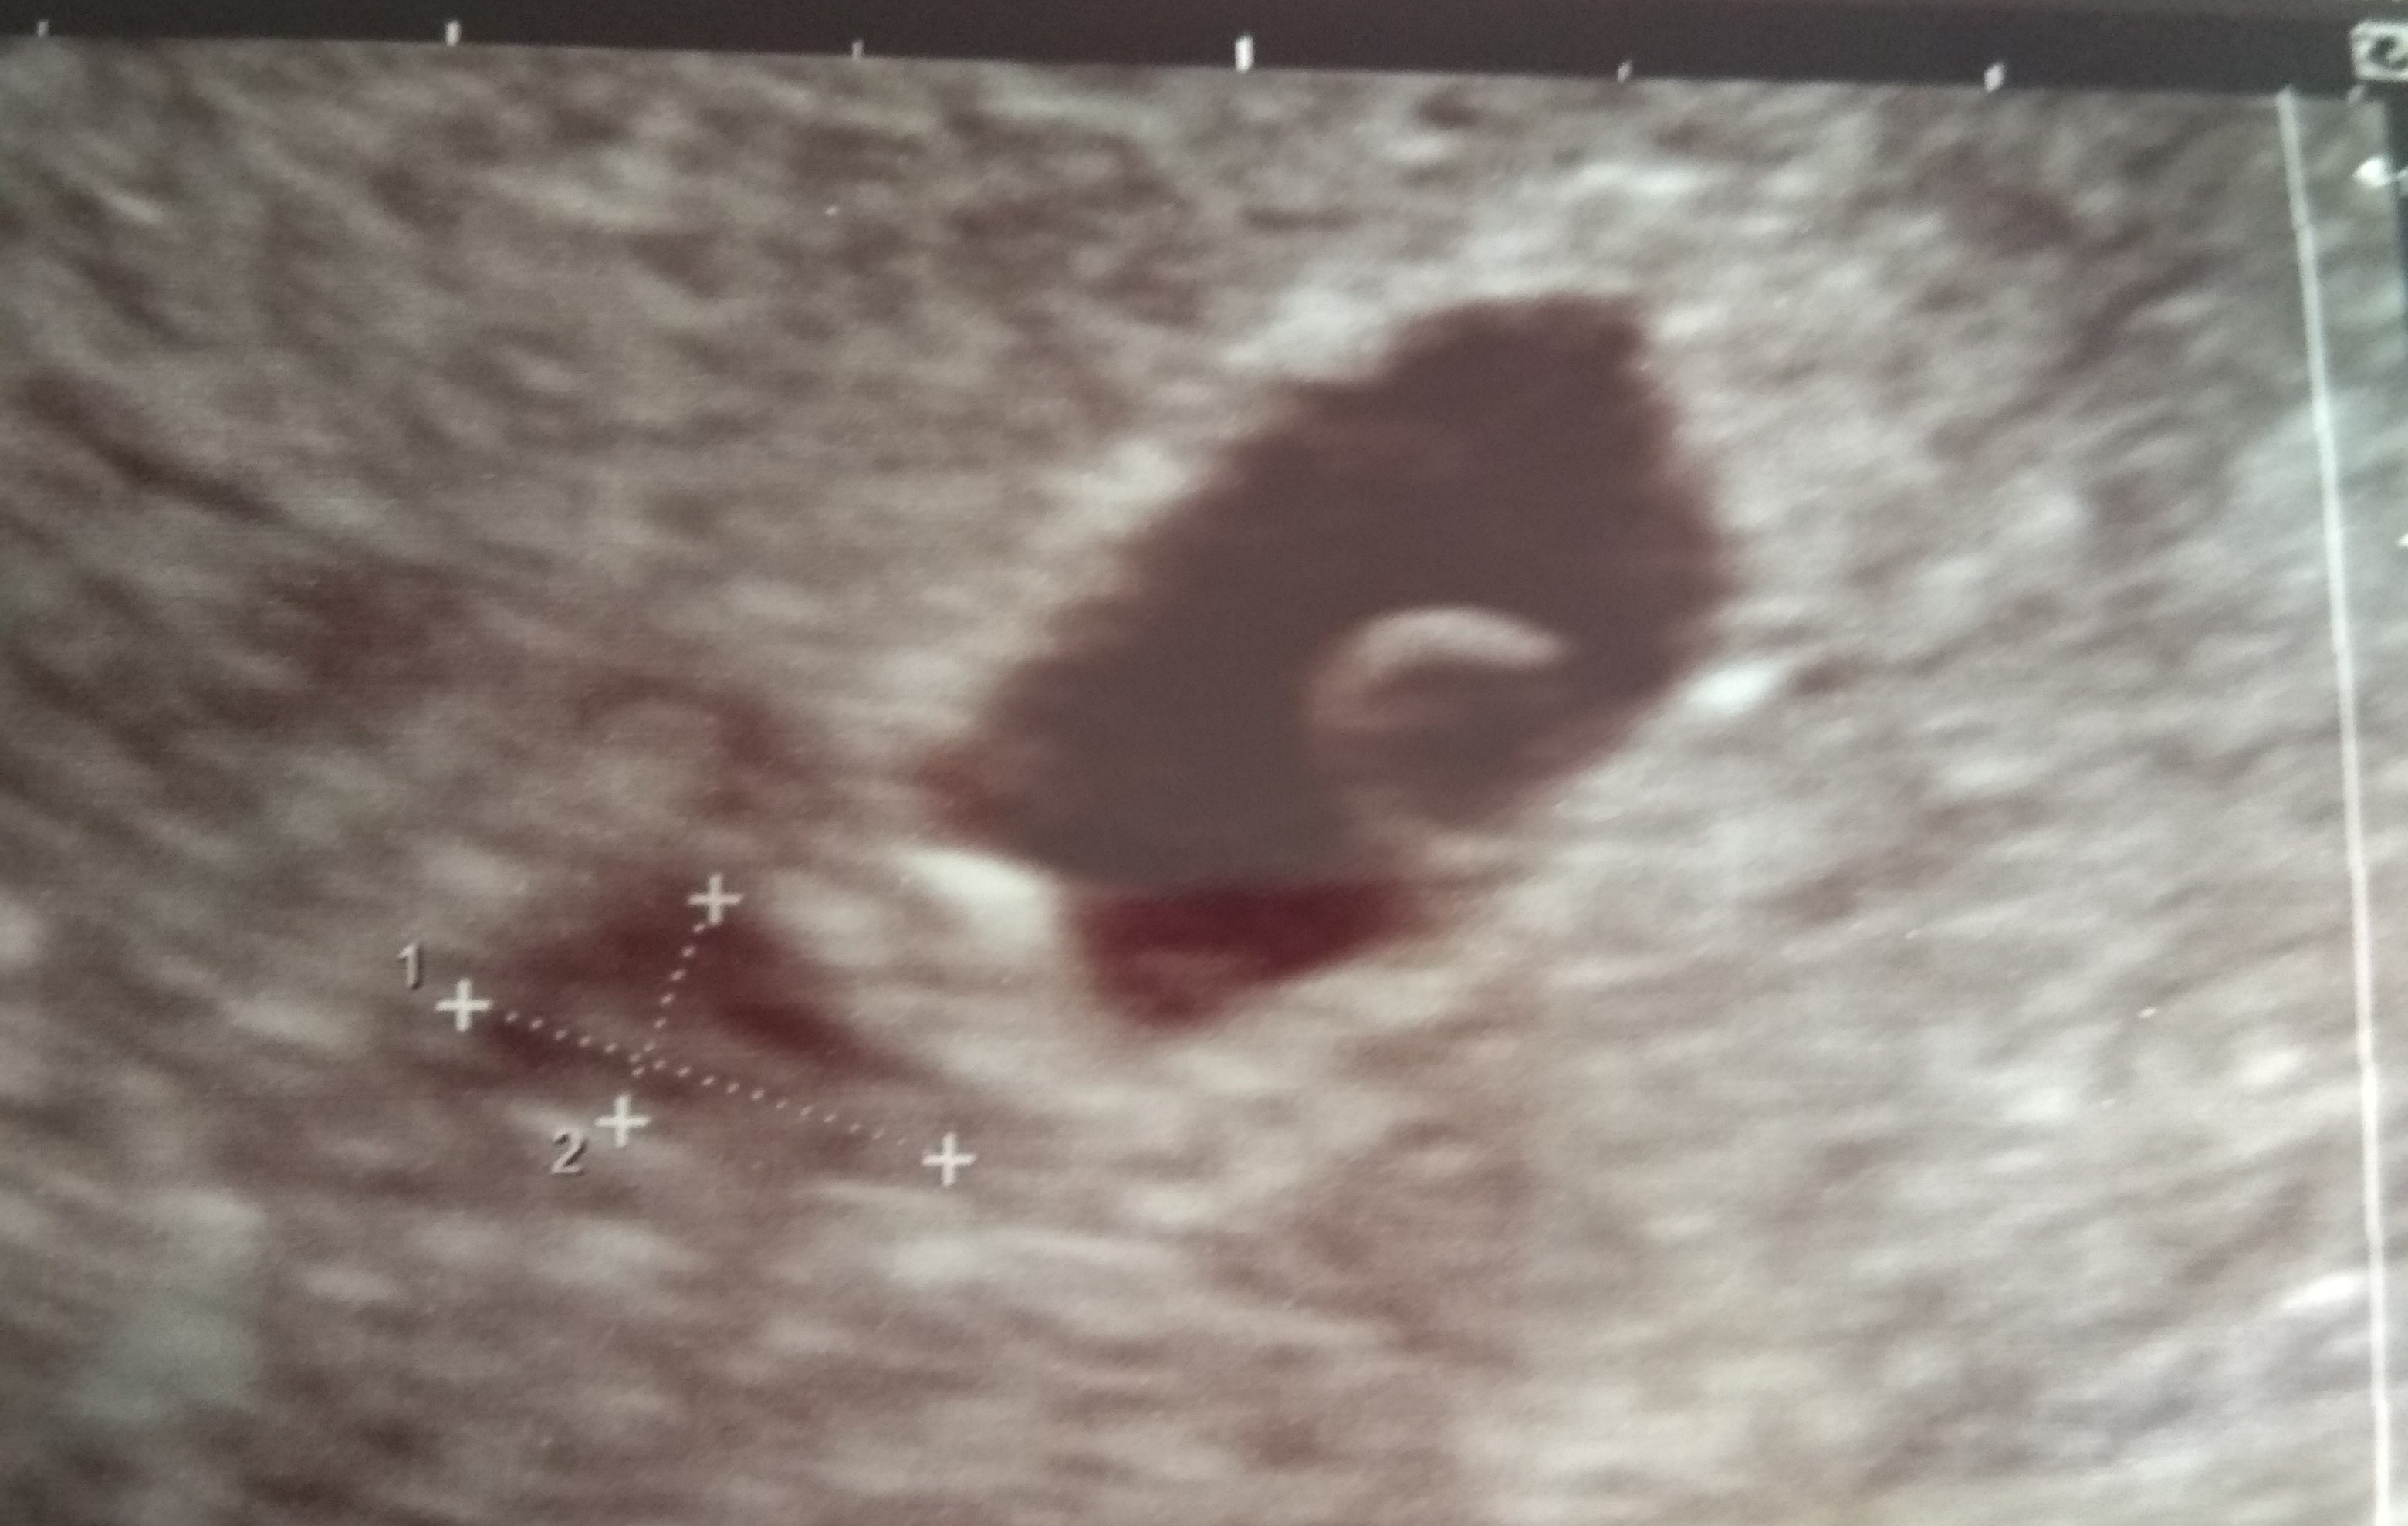

Jeżeli ciąża jest te dwa dni młodsza to nie musi być widać jeszcze zarodka. Podobno po 6 tygodniu widać zarodek. Około 7 tygodnia widać czynność serca.

Nie chcę nikogo stresować, bo każda ciąża jest inna ale u mnie w 5t3d był taki obraz USG i zarodek

Załączniki

• IMG_20210430_140207.jpg

Powinnaś 🙂 ja poszłam w połowie 5 tygodnia i był zarodek. Niby wcześnie ale lekarz i ja się cieszyliśmy, bo mam małego krwiaka i dostałam kilka zaleceń 🙂 powiedział, że w 2 tygodnie powinien się ładnie wchłonąć i tej wersji się trzymam 🙂 czwartek jak wyrocznia 😂